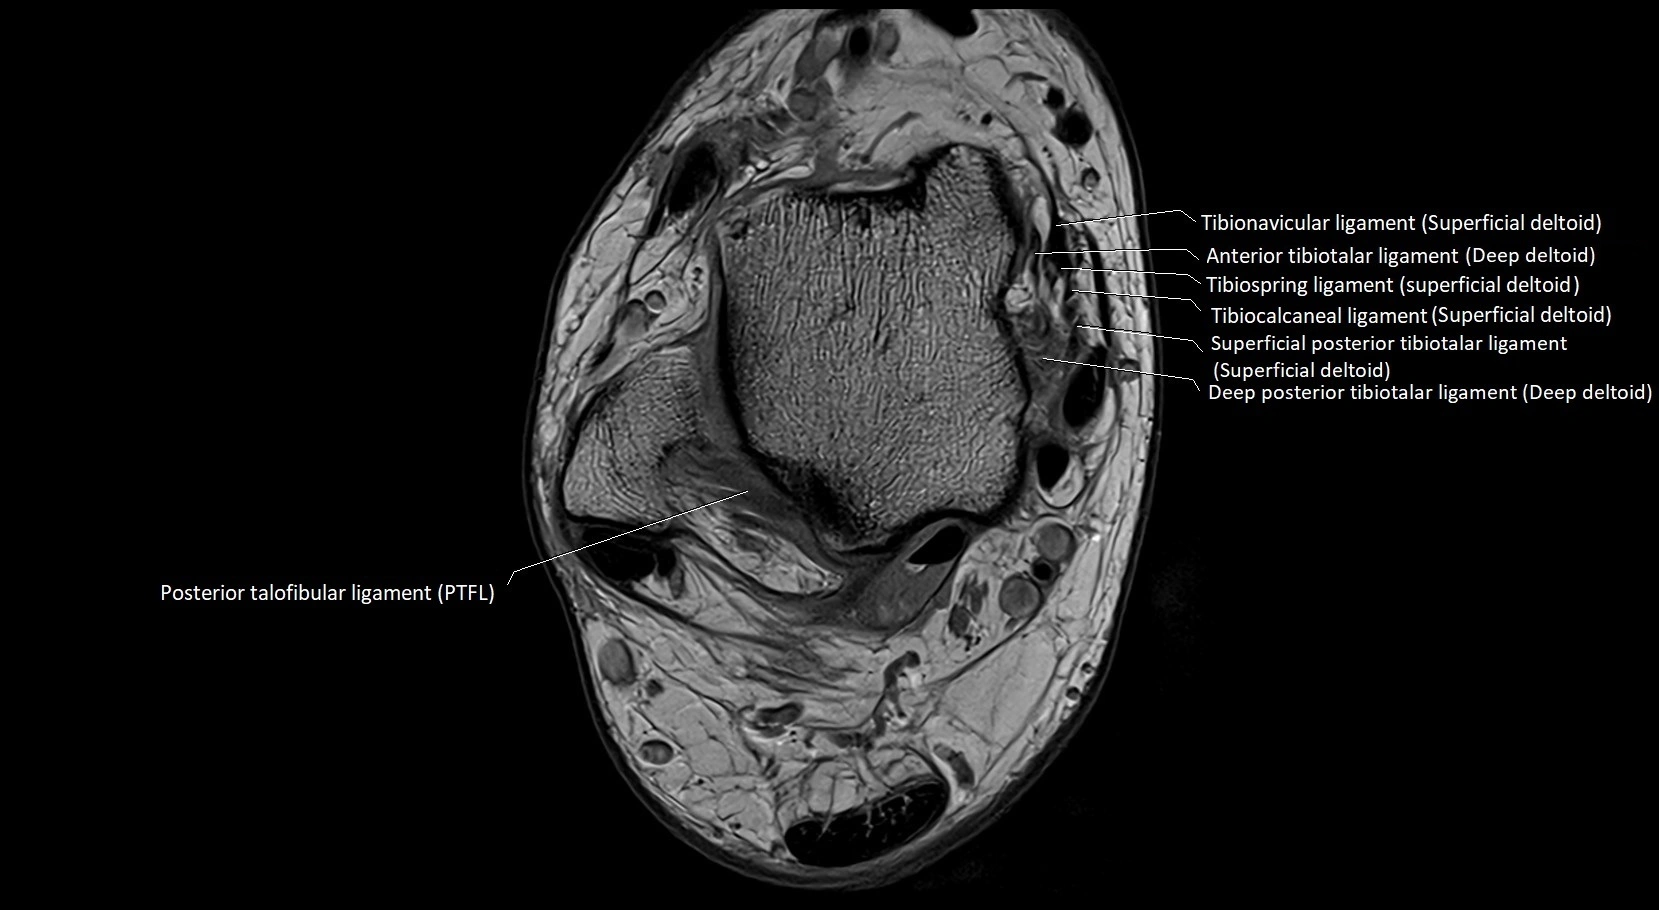

MRI image

image